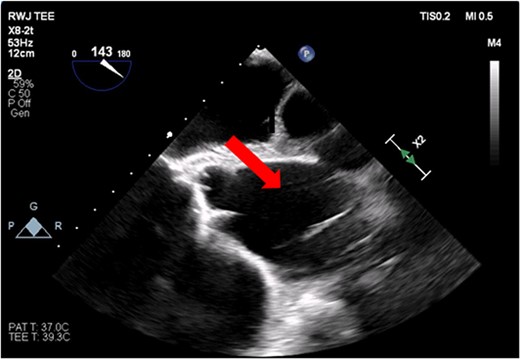

The patient’s milrinone dose was unable to be increased due to his risk for VT and his marginal blood pressures. A 50 cc 8 French left axillary IABP with proximal and distal markers was placed under fluoroscopy and transesophageal echo (TEE) guidance to prevent worsening of end-organ dysfunction and cardiogenic shock. About 3.5 weeks later, the patient received a heart transplant. His 20 gauge right radial arterial catheter was used for monitoring. There were no identifiable changes in the arterial line and the pressure waveforms. The patient was ambulatory in the intensive care unit (ICU) and showed no signs of decreased perfusion. After induction of general anesthesia, TEE showed the IABP in his aortic arch and ascending aorta with its tip placed proximally in the descending aorta (Figs 1 and 2).

Transesophageal image of the ascending and descending aorta with mispositioned IABP present.